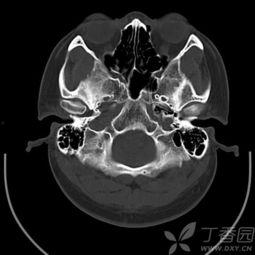

首先,让我们来看看正常鼻骨CT图片的基本结构。这张图片上,你的鼻骨清晰可见,就像是一幅精细的地图。鼻骨位于鼻子的中央,是面部骨骼的一部分。它由两个长条形的骨头组成,形状像字母“V”。

在正常鼻骨CT图片上,你可以看到以下特点:

1. 鼻骨的形状:鼻骨呈长条形,两端较细,中间较粗。

2. 鼻骨的厚度:正常鼻骨的厚度大约在1.5到2.5毫米之间。

3. 鼻骨的密度:与周围骨骼相比,鼻骨的密度略低,但仍然较为致密。

4. 鼻骨的对称性:正常情况下,左右两侧的鼻骨大小、形状和密度基本一致。